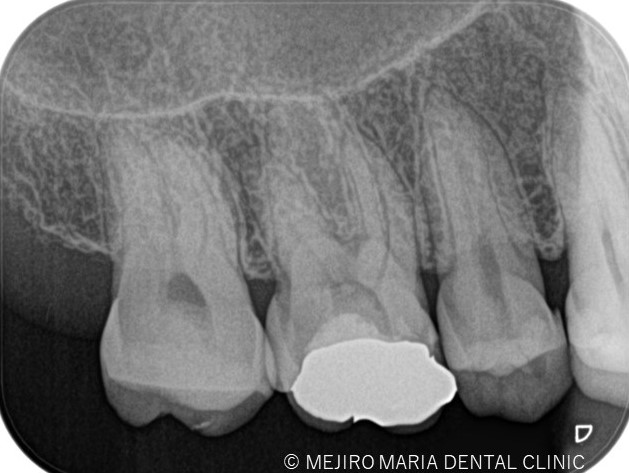

歯科用拡大鏡、歯科用顕微鏡下にて、軟化象牙質(虫歯)を除去後、歯髄を確認すると一部の歯髄には血流がなく部分壊死を起こしていることがわかる。

|歯の寿命を左右する初回根管治療_術前術後のレントゲン画像比較-1024x756.jpg)

根管治療において初めての根管治療(抜髄処置)が、その後の歯の寿命を左右する非常に大切な治療になります。 しっかりとコンセプトに沿った根管治療を行うことでより将来的な根尖性歯周炎(骨の中にまで炎症が進行しご自身の歯を残せなくなる場合もあります)になるリスクを最小限に抑えることができます。